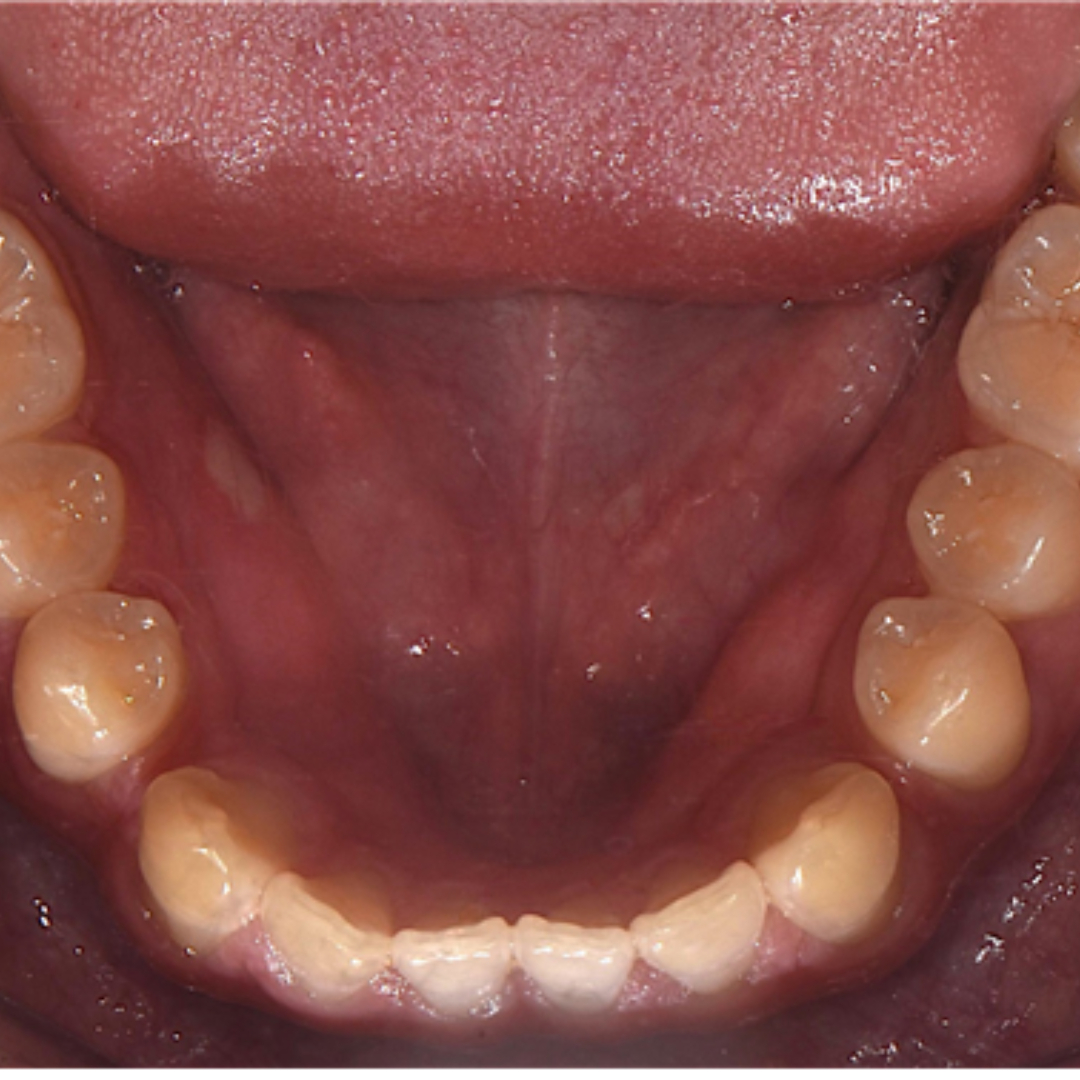

앞니 사이 벌어진 공간과 정중선 불일치를 고민으로 내원하셨던 20대 남성 환자분입니다. 윗니, 아랫니 공간이 각각 3.4mm, 2.6mm 가량 벌어져있고, 위와 아래의 중앙선 차이가 2.1mm 정도로, 상대적으로 정중이개와 정중선 불일치가 눈에 띄는 모습입니다. 해당 환자분께서는 격투기를 취미로 하시는 분이셔서 교정장치를 부착한 채로 얼굴 부위에 타격이 있을 경우 입 안이 다칠까봐 걱정이 있으셨습니다. 교정 진단 상담 후 고민 끝에 부상 방지를 위해 표면이 매끈한 투명교정 장치로 치료하시기로 결정하셨습니다.

최근에는 티 나지 않는 교정을 원하시는 심미적인 이유 뿐만 아니라, 위생 관리, 음식물 섭취, 부상 방지 등 다양한 이유로 전통적인 부착식 교정장치 대신 투명 교정을 선택하시는 환자분들이 부쩍 많아지셨습니다. 투명 교정 치료는 결과는 동일하면서 사진 촬영, 운동, 여행 등 일상 생활에 제약이 크게 없다는 점이 큰 장점입니다. 다만, 증례에 따라 부착식 교정장치가 더 빠르고 효과적인 경우도 있어 교정 치료 전 전문의와의 상담을 통해 결정하는 것이 좋습니다. ^^ 총 32주 간의 교정 치료가 종료된 모습입니다. 기존에 가장 고민이셨던 공간 벌어짐, 정중선 불일치가 예쁘게 수정되었습니다. 2025.5.18.